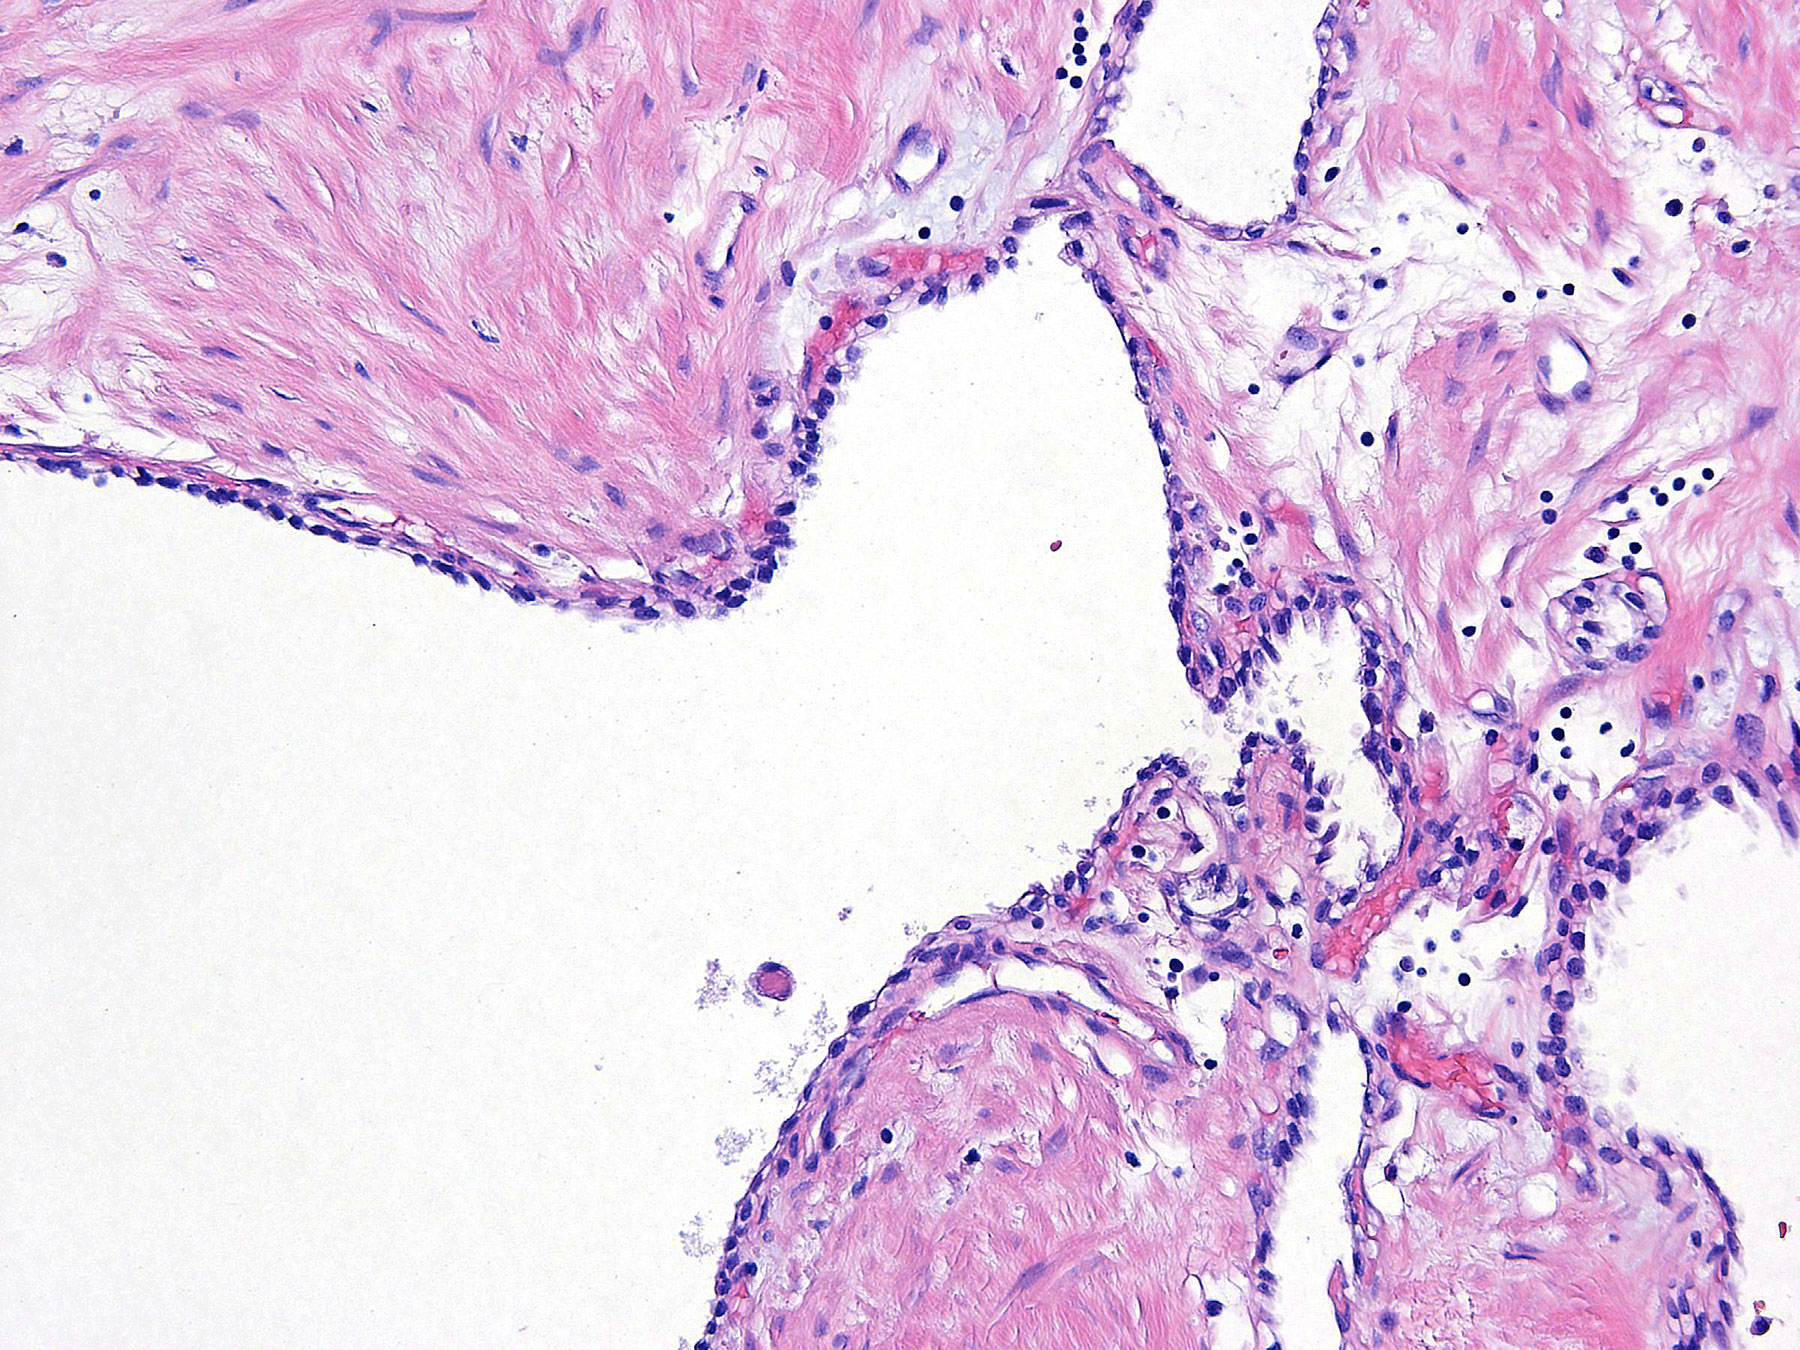

Figure B. H&E x20

Histology: The sections show several cystic structures lined by single layers of flattened and cuboidal cells separated by fibrous septa.